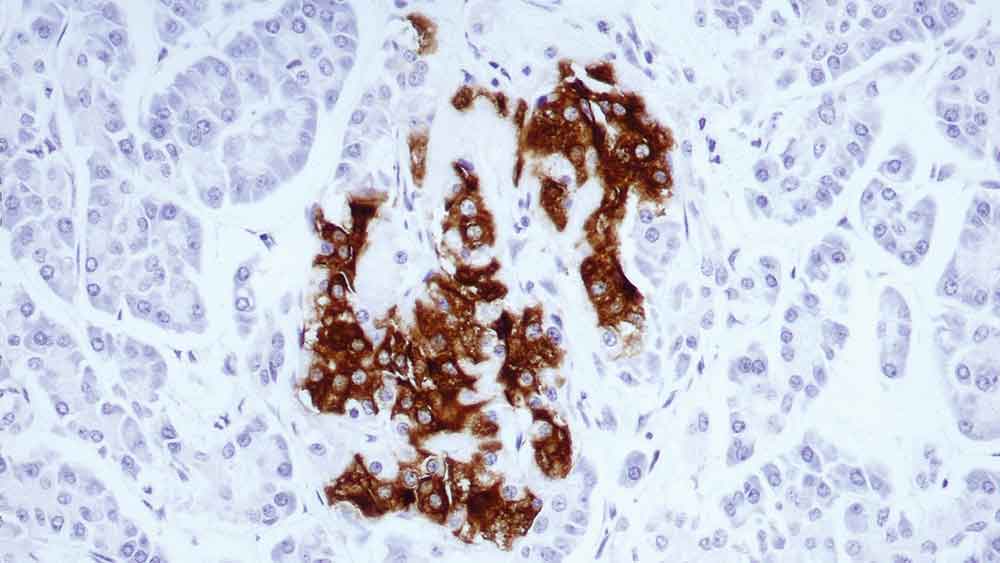

Human pancreas: immunohistochemical staining for insulin-containing cells. Note intense cytoplasmic staining. Insulin: clone 2D11-H5

Insulin ist ein Hormon, das von den Beta-Zellen der Langerhans-Inseln in der Bauchspeicheldrüse sekretiert wird. Es fördert die Glykogenspeicherung, die Bildung von Triglyceriden und die Synthese von Proteinen und Nukleinsäuren.

Immunzytochemische Untersuchungen haben das Vorhandensein von Insulin im Zytoplasma bestimmter Inseltumore gezeigt.

In einigen Fällen sind die insulinpositiven Granula spärlich vorhanden und bilden einen Rand entlang der Zellmembran.